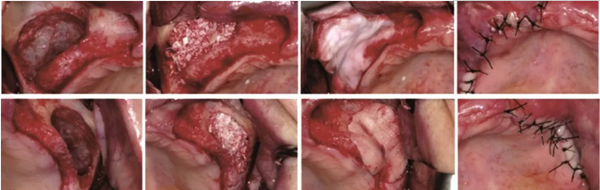

1、CGF/PRF作為屏障膜使用

在引導骨再生術中,需要使用可吸收或不可吸收的屏障膜,為骨組織的再生提供不受干擾的空間。如果使用CGF/PRF作為屏障膜,其相對目前臨床使用的可吸收生物膜是否具有優(yōu)勢?Gassling等進行了一項臨床研究[4],研究納入了6例需要進行雙側上頜竇外提升的患者,在完成植入骨替代材料后,一側使用PRF壓制而成的屏障膜覆蓋開窗處,而另一側則使用目前臨床廣泛使用的Bio-Gide生物膜覆蓋,如圖1示,以對比兩者的差異。作者發(fā)現(xiàn),術后患者兩側水腫、疼痛及初期創(chuàng)口愈合情況無明顯差異,術后5個月行種植體植入術時,作者同時取出部分骨組織行組織學評估,發(fā)現(xiàn)兩組在新生骨的比例和骨替代材料的剩余比例上均無差異。

學者研究發(fā)現(xiàn),單獨使用CGF/PRF作為屏障膜,因為其降解速度較快,無法達到理想的屏障效果。當聯(lián)合生物膠原膜使用時,未見明顯的促進成骨效果,同時增加了手術費用和手術難度。亦有學者表示CGF/PRF作為膜使用,聯(lián)合生物膠原膜應用于GBR植骨術中時,可以促進局部軟組織的愈合,降低感染的幾率。